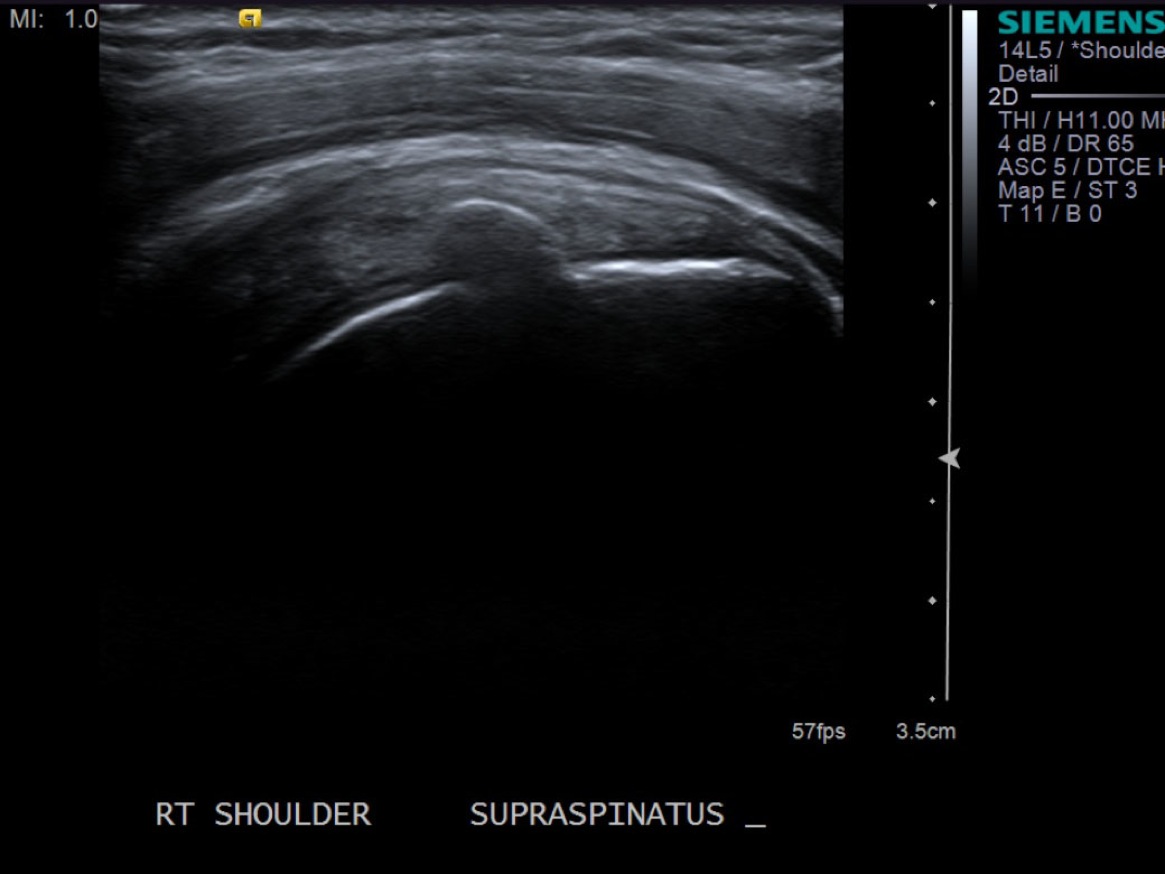

• descriptiondescription

Short axis view of supraspinatus tendon with calcific deposit